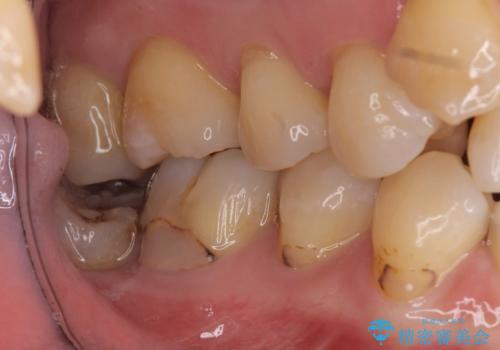

詰め物の下が虫歯 つぎはぎの歯をしっかり治療